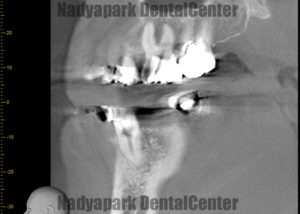

こちらの患者さんは、左下緑矢印の歯を他院で3年根管治療を続けているが違和感が消えないということで来院されました。

この歯が今どんな状態なのか?残すことが出来るのか?診断をするために歯科用CT撮影を行いました。

CTを撮って確認したところ、根尖病巣(根っこの先に炎症や膿がある状態)はなさそうだったので保存可能と判断し、患者さんの希望もありマイクロスコープを使った根管治療を開始することになりました。